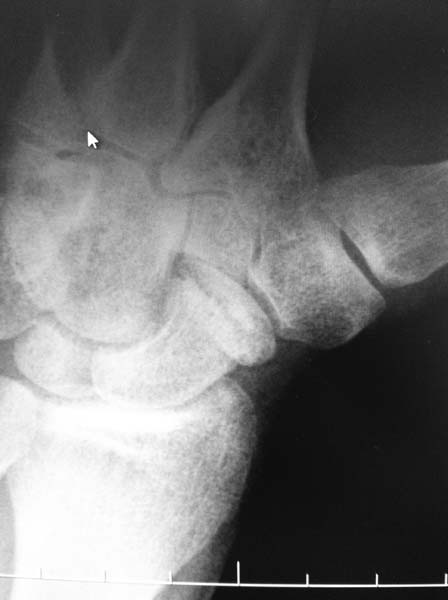

Пациент 21год, обратился через 6 месяцев после травмы с жалобами на ограничение движений и боль в области кистевого сустава. На рентгенограммах видно, что размер дистального отломка ладьевидной кости невелик, в связи с чем возникает вопрос: есть ли смысл делать аутопластику костным штифтом или показано удаление дистального отломка? Сомнения возникли в связи с возможными техническими трудностями (вероятность расколоть столь малый отломок при формировании канала), да и вообще перспектив сращения такого рода ложного сустава. Заранее благодарен за ответы. С уважением.